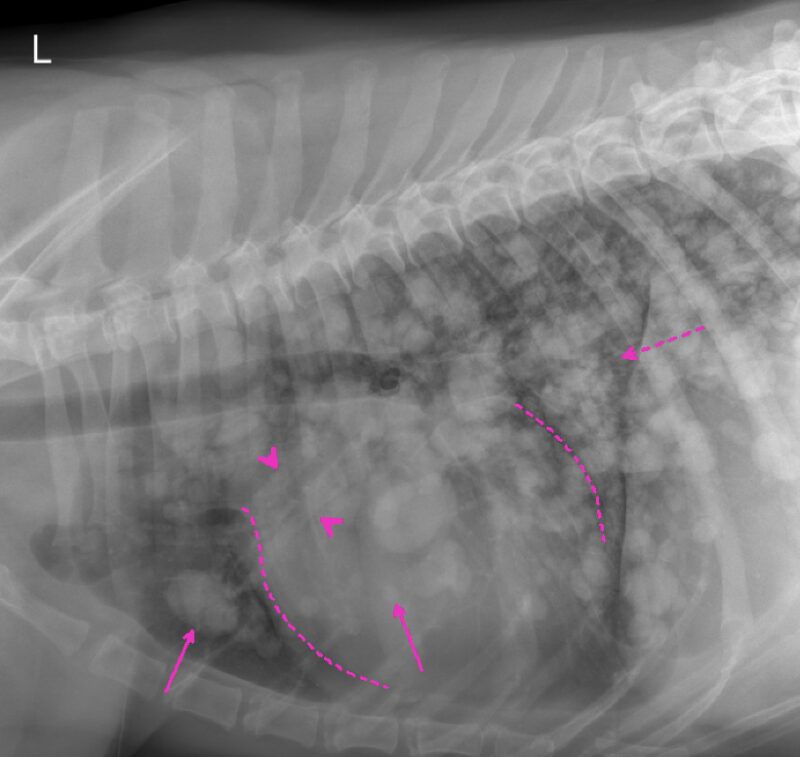

Vielen Dank für die Zusendung der Röntgenbilder. Ein wirklich eindrucksvoller Fall! Es liegen zwei Röntgenaufnahmen des linken Humerus, inkl. Ellbogengelenk, im medio-lateralen, sowie kaudo-kranialem Strahlengang vor. Begleitend besteht eine Röntgenaufnahme des Thorax in dextro-sinistralem Strahlengang (Abb. 1, Abb. 2). Im Röntgenbild der linken Vordergliedmaße zeigt sich im Bereich der gesamten Diaphyse des Humerus, bis in die angrenzenden metaphysären Abschnitte reichend, eine hochgradige, unregelmäßige osteoproliferative Reaktion (blaue Pfeile Abb. 3). Diese periostale Reaktion weist eine heterogene Röntgendichte auf. An ihrer ausgeprägtesten Stelle übersteigt die Proliferation den Durchmesser des normalen Humerus deutlich. Besonders an der kaudalen Humeruskontur besteht hochgradige, laminar geschichtete Knochenneubildung (gelbe Pfeile, Bild links).

Die Markhöhle (Medulla) erscheint hochgradig heterogen (blaue Pfeilköpfe). Entlang des Endosteums sind multifokale Irregularitäten (grüne Pfeilköpfe), sowie multifokale kortikale Lysen (rote Pfeile) sichtbar, die den Befund einer destruktiv-proliferativen Knochenerkrankung verdeutlicht. Eine pathologische Fraktur ist in den vorliegenden Aufnahmen nicht erkennbar.

Das umgebende Weichteilgewebe zeigt eine deutliche Umfangsvermehrung (hellgelbe Pfeile und Pfeilköpfe, Bild rechts). Zudem findet sich am proximalen Radius eine geringgradige, glattrandige periostale Reaktion (gelbe Pfeilköpfe, Bild links).

Im Thoraxröntgen zeigen sich in allen Lungenlappen multifokale, noduläre Weichteilverschattungen unterschiedlicher Größe, wobei die größte eine Länge von 3,8cm und eine Breite von 2,6cm aufweist (exemplarisch pinke Pfeile). Generalisiert besteht zudem vor allem in den kaudalen Lungenlappen geringgradige (pink gestrichelter Pfeil), sowie im akzessorischen Lungenlappen moderate unstrukturierte Lungenzeichnung. Die Herzsilhouhette ist generalisiert globoid vergrößert (pink gestrichelte Linien). Die kranialen Lungengefäße wirken prominent, sind jedoch kleiner als die proximale Breite im Bereich der vierten Rippe (pinke Pfeilköpfe). Mediastinale Strukturen, Pleuralraum, Trachea, Ösophagus, sowie sichtbare ossäre Anteile stellen sich ohne besonderen Befund dar.